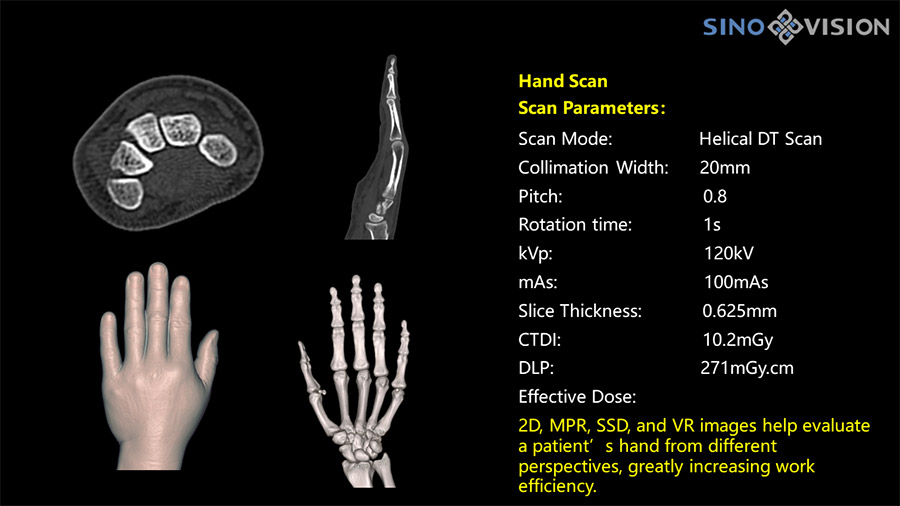

Компьютерные томографы SinoVision обеспечивают удобное размещение пациентов, превосходную визуализацию структур, включая мелкие сосуды, и низкую лучевую нагрузку.

- Высокое разрешение

Подходят для решения сложных задач общей диагностики, хирургии, сосудистой визуализации, моделирования и биопсии при онкологии.

Программное обеспечение на базе ИИ позволяет проводить постобработку с использованием облачных хранилищ и технологий удалённой диагностики, оценку морфологии, качественный анализ с помощью технологии спектральной визуализации.